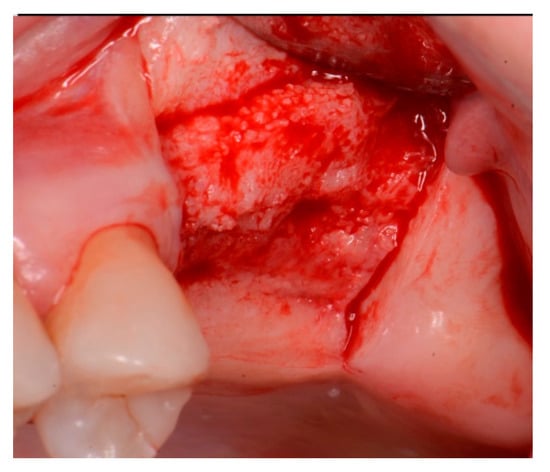

A critical question is about what happens histologically to the graft and at what stage during healing. For example, when delayed socket grafting was performed at a site where a large defect was present following extraction (Figure 18, left), a healing period of 3 weeks post-extraction was needed, allowing primary closure post-graft. This gives us more predictability and simpler surgery, plus two attempts to clean the site. EthOss graft material was placed into the socket (Figure 18, middle) and primary closure with the flap was achieved and secured with sutures (Figure 18, right). Intraoral physical exam and radiographic measurement showed all sites to have regenerated vertically 3–6 mm and horizontally 4–6 mm with new host bone allowing for successful placement of the implants. A core sample was obtained from one case to confirm the series to be in line with earlier findings. Histology was performed by core biopsy at 10 weeks following graft placement and demonstrated well-preserved reactive (woven) trabecular bone with intertrabecular tissue composed of uniformly collagen-rich myofibroblastic tissue and 60% of the core consisting of bone (Figure 19).

Figure 18.

Delayed socket grafting with flap exposure of the site (left), placement of EthOss graft to fill the defect (middle) and flap placement to achieve primary closure (right).